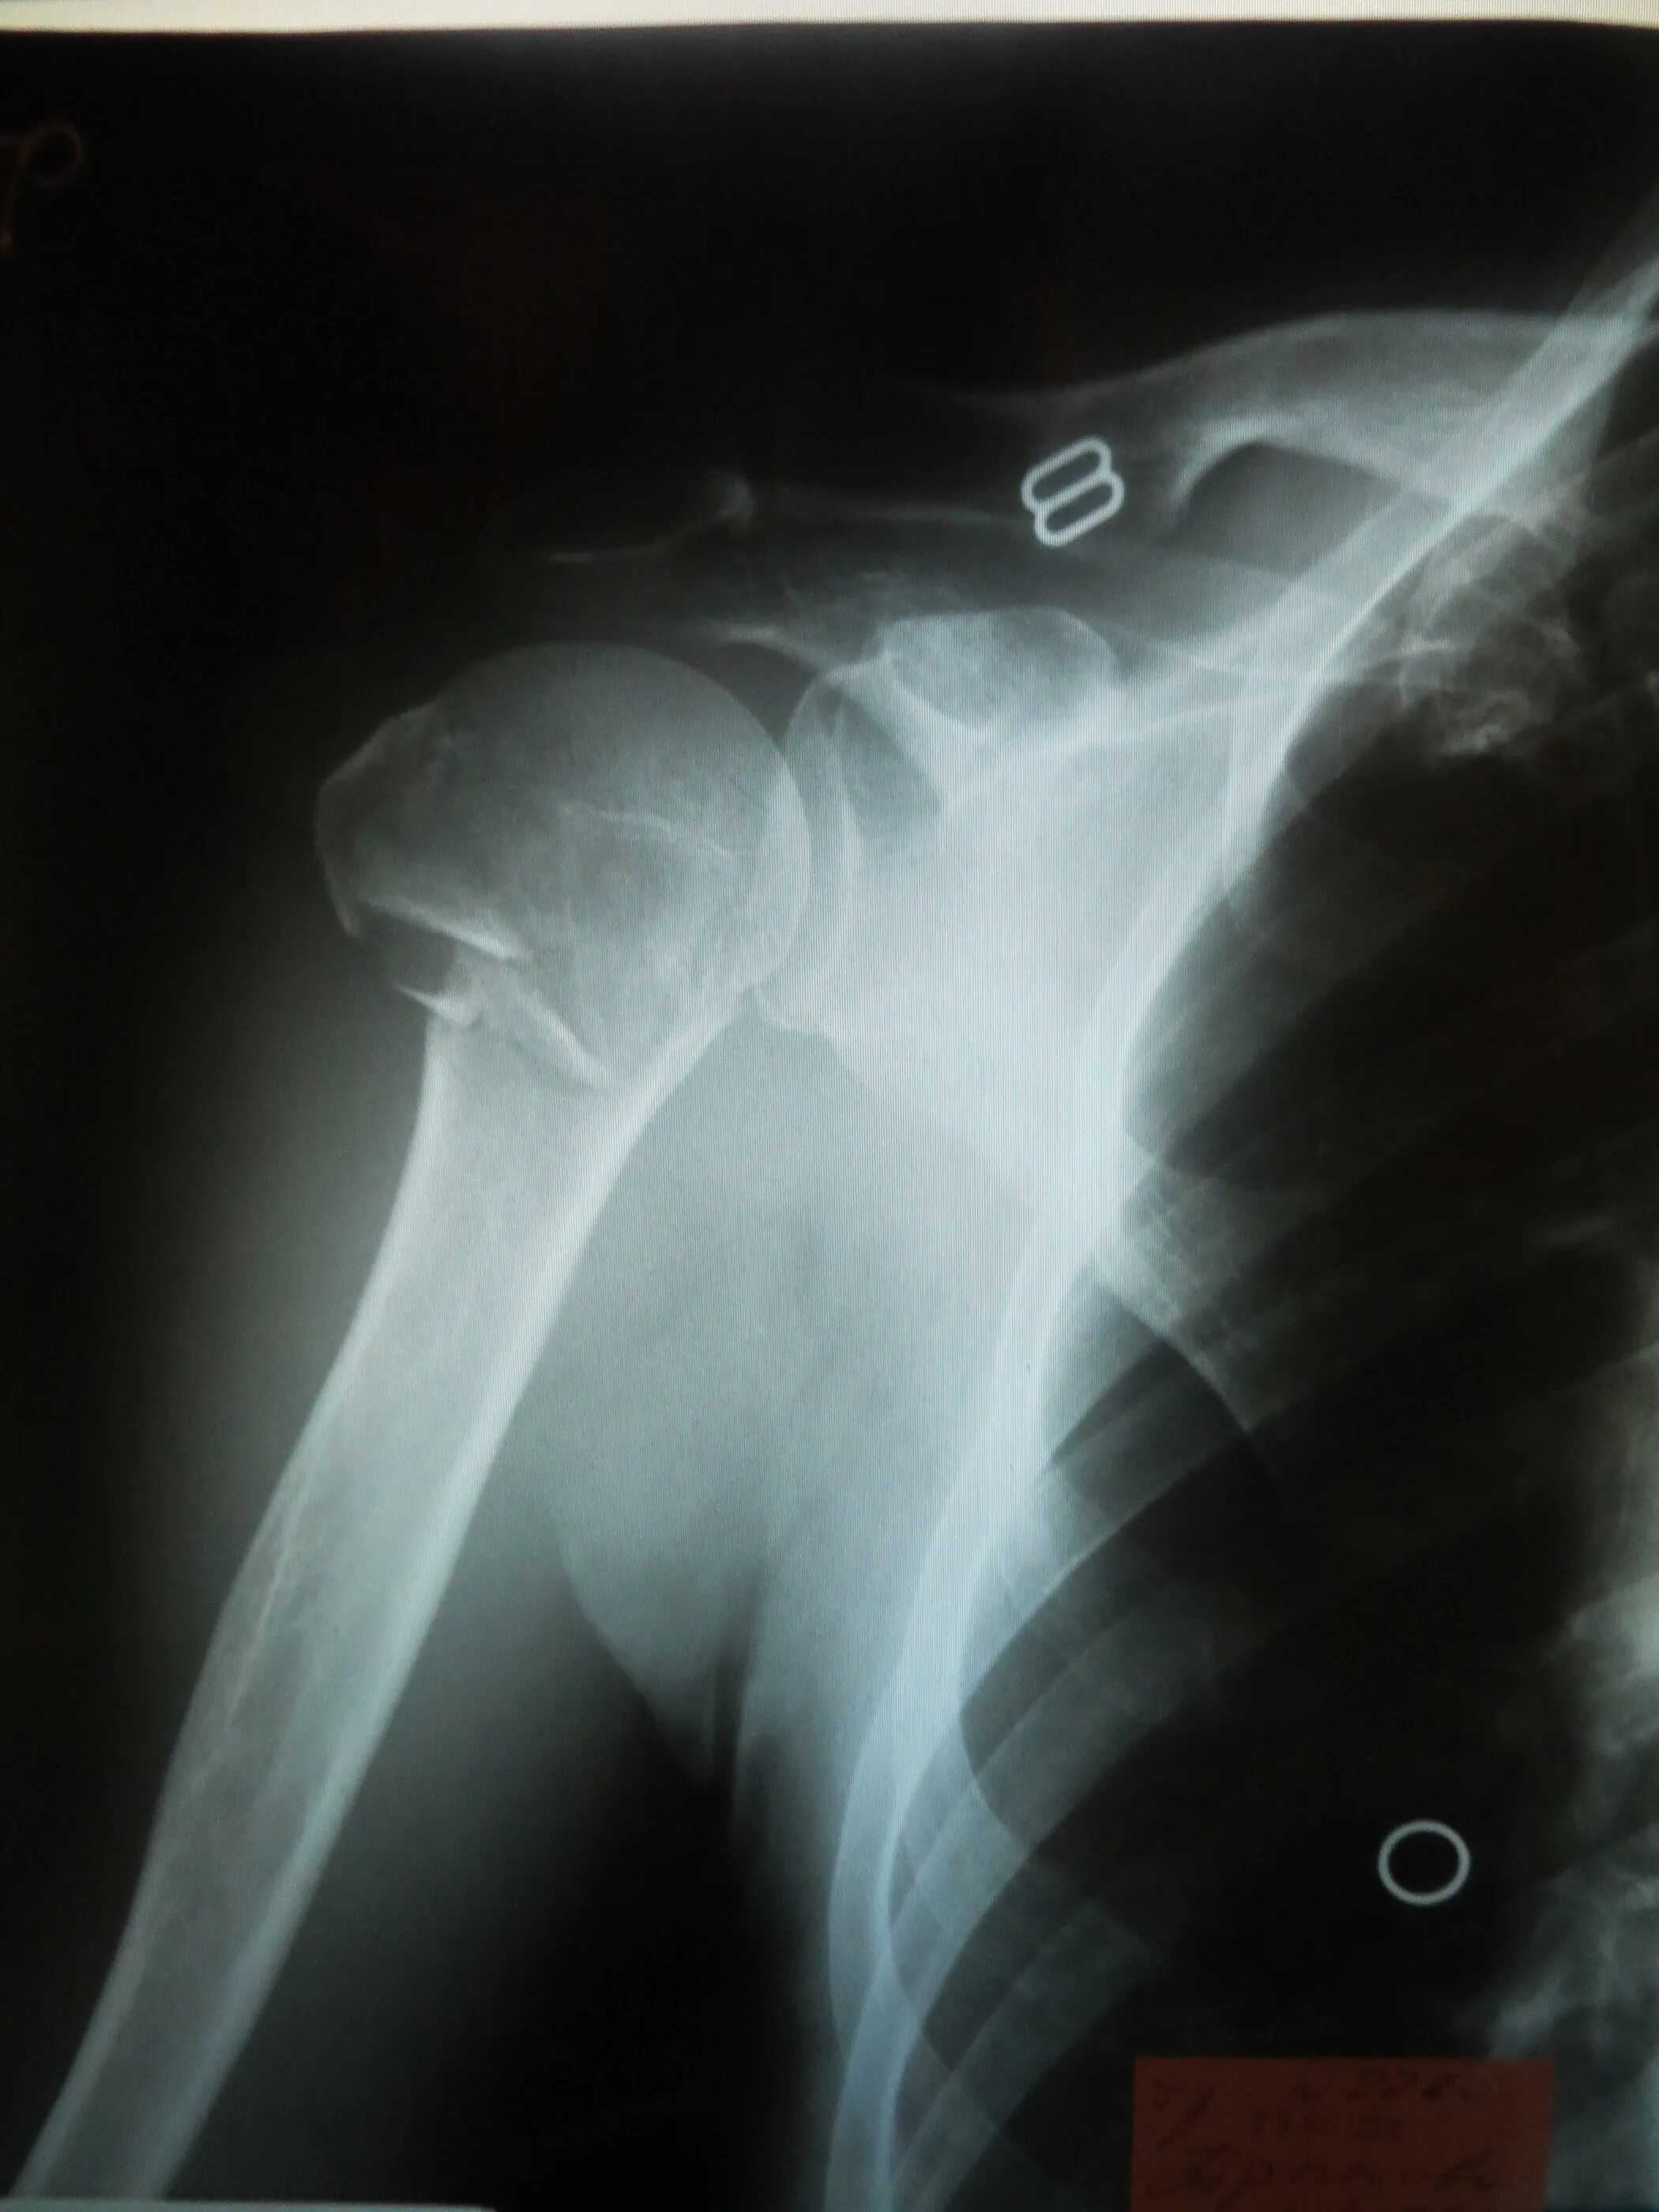

Сколько срастается плечевой перелом